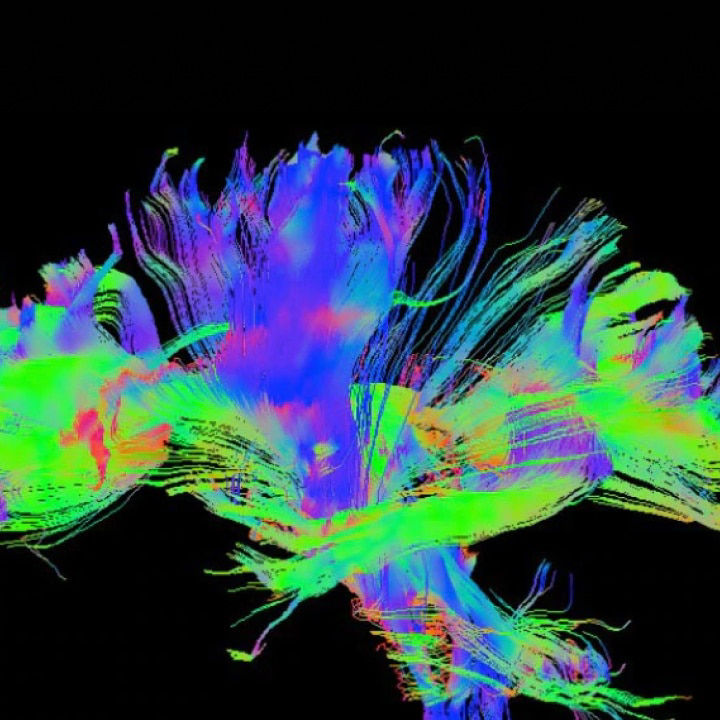

Our boldest ideas yet

Meet our next-generation SIGNA MRI scanners & solutions

SIGNA MRI Scanners

Our 1.5T, 3T, PET/MR and 7T scanners deliver the latest in imaging innovation with AIR Recon DL, and AIR Coils.